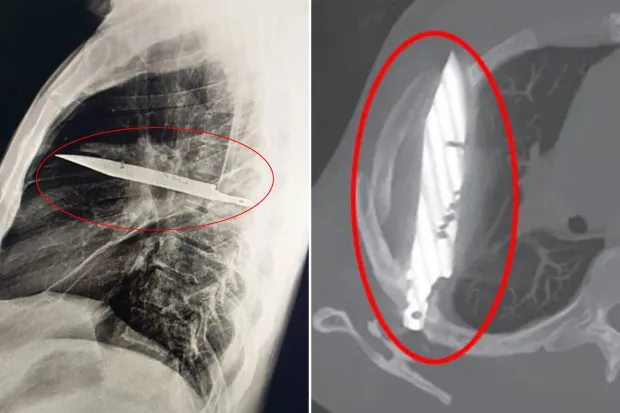

แพทย์ไม่สามารถหาสาเหตุของการติดเชื้อได้ จึงสั่งตรวจเอกซเรย์ และก็ต้องตกใจเมื่อพบใบมีดขนาดใหญ่ฝังอยู่ในหน้าอกของชายคนนั้น

จากภาพเอกซเรย์ด้านข้างทรวงอก พบวัตถุโลหะฝังอยู่ในส่วนกลางทรวงอก โดยมีลักษณะขุ่นทึบล้อมรอบ ซึ่งอาจเป็นเลือดที่คั่งค้างหรือเนื้อเยื่อพังผืดที่เกิดจากการบาดเจ็บเรื้อรัง

ใบมีดซึ่งทะลุเข้ามาทางกระดูกสะบักด้านขวาได้อย่างน่าอัศจรรย์ ได้หลบเลี่ยงอวัยวะสำคัญทั้งหมดไปได้ ในขณะที่เกิดเหตุการณ์เมื่อ 8 ปีก่อน โรงพยาบาลที่เขารักษาไม่มีเครื่องมือในการตรวจทางรังสี และเนื่องจากเขาไม่มีอาการเจ็บปวดหลังจากแผลหาย จึงไม่มีใครตรวจสอบเพิ่มเติม ที่น่าแปลกใจยิ่งกว่านั้นคือ ใบมีดไม่ได้ทำให้ผู้ป่วยวัย 44 ปี ผู้นี้รู้สึกไม่สบายเลยเป็นเวลานาน หนองที่ไหลออกมาเป็นผลมาจากเนื้อเยื่อที่ตายแล้วซึ่งสะสมอยู่รอบๆ วัตถุแปลกปลอม